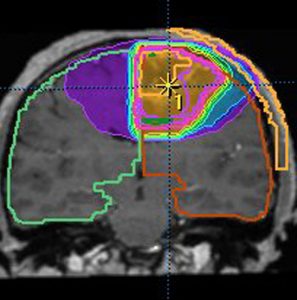

放射線治療計画の等線量曲線 isodose curves です

腫瘍とその周辺にどの程度の線量(グレイ)を当てるかを計画します

赤紫の線で囲われた部分が,実際に計画線量をかける部分(照射野,PTV)です

グリオーマでは,MRIでみえている腫瘍範囲よりかなり広い領域の正常脳にも放射線がかかります